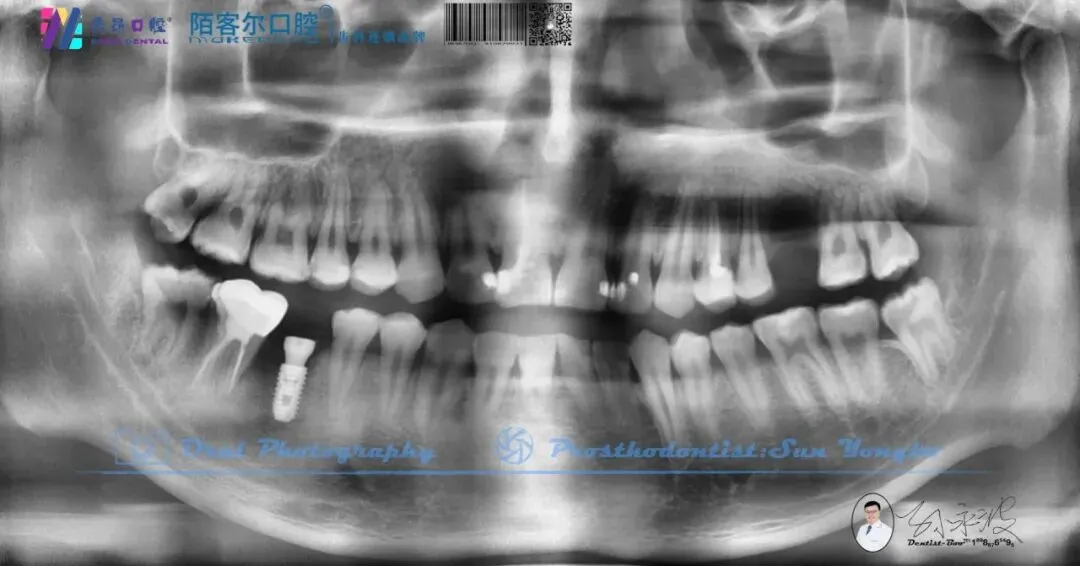

>【深圳牙医-孙永波】病例16丨右下后牙单颗缺失种植修复

【深圳牙医-孙永波】病例16丨右下后牙单颗缺失种植修复